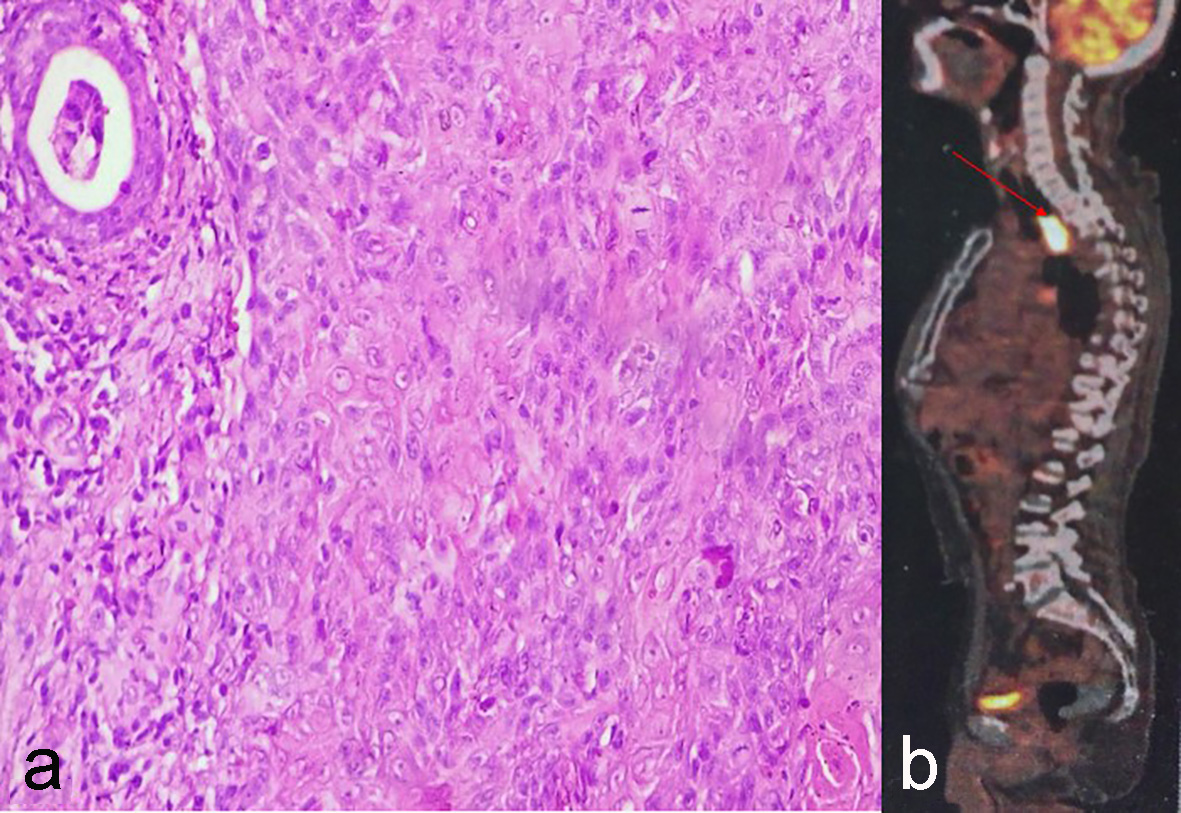

A 65-year-old male presented in January 2002 with lump in right breast for 2 months. He was diagnosed with carcinoma breast, was operated and received six cycles of adjuvant chemotherapy with cyclophosphamide, adriamycin, 5-flurouracil (CAF) and external beam radiotherapy (50 Gy in 25 fractions) to chest wall, axilla, supraclavicular and internal mammary portals by cobalt 60. Patient was asymptomatic during follow-up. In June 2016, patient presented with complaints of difficulty in swallowing solid and semisolid food. Upper gastrointestinal endoscopy showed an ulcerative growth with luminal narrowing at a distance of about 22 cm from incisor. Biopsy was done and histopathological examination (HPE) revealed moderately differentiated squamous cell carcinoma (MDSCC) (Fig. 1a). Whole body positron emission tomography-contrast-enhanced computed tomography (PET-CECT) revealed fluorodeoxyglucose (FDG) avid mass lesion in esophagus, about 3.5 cm in craniocaudal dimension (Fig. 1b). According to the age and Karnofsky performance score (KPS) 50, patient was planned for palliative radiotherapy to esophagus, but the patient expired before receiving treatment.

![]() Click for large image | Figure 1. (a) Moderately differentiated squamous cell carcinoma. (b) PET-CECT showing FDG avid mass lesion in esophagus at level of D2-D4. |